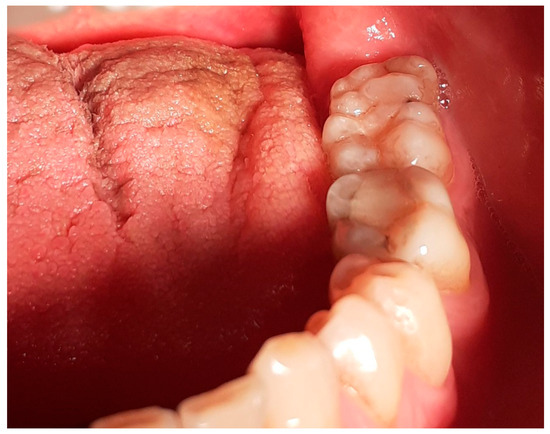

The crown of the atypical molar exhibited eight cusps (Figure 3). There were four buccal and four lingual cusps: the sizeable mesio-buccal cusp, middle-buccal (small-sized), disto-buccal (sizeable, located towards the middle of the occlusal surface) and the disto-buccal-angle cusp (located at the buccal–distal angle); the mesio-lingual cusp, middle-lingual, disto-lingual (small-sized) and the disto-lingual-angle cusp, which seemed to be composed from two smaller cusps, divided by a shallow fissure. The shape of the cusps was similar to the shapes of the mandibular molar cusps, and their positions in the occlusal surface also resembled the normal ones, with the exception of the buccal–distal cusp, which had a flattened ridge and a vertical bucco-lingual orientation resembling a large marginal ridge. This was the second biggest cusp in size, following the mesio-buccal cusp, which was the biggest. The fissures of the occlusal surface were deep and enhanced, and there were no signs of erosion. The atypical molar was occluded with the first and second maxillary left molars.

The molar had a rectangular shape, with the mesio-distal dimension being the longest. The mesiodistal and buccolingual diameters were measured with a dental caliper: the mesiodistal dimension measured between the contact points of the proximal surfaces was 14.8 mm and the buccolingual dimension measured between the buccal and lingual crests was 10.7 mm. For reasons of comparison, the neighboring molar located mesially to the atypical one had mesiodistal dimension of 12 mm and buccolingual of 10 mm.

Figure 1. Intraoral photograph, left mandibular posterior area.